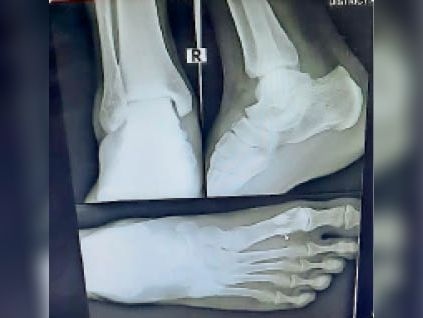

दिल्ली| ग्रेटर नोएडा वेस्ट की सुपरटेक ईकोविलेज एक सोसायटी में बिजली जाने से लिफ्ट 13वीं से आठवीं मंजिल पर जाकर गिर गई। लिफ्ट में सवार 65 वर्ष की बुजुर्ग महिला अपने नाती और नातिन के साथ थीं। लिफ्ट गिरने से बुजुर्ग महिला के पैर में चार फ्रैक्चर हुए हैं। आरोप है कि बुजुर्ग को मौके पर व्हीलचेयर तक नहीं मिलीं। वह किसी तरह अपने घर तक पहुंची। उन्होंने परिवार के लोगों को घटना के बारे में बताया। परिवार के लोग उपचार के लिए उन्हें अस्पताल ले गए। जहां एक्सरे कराने पर चार फ्रैक्चर की पुष्टि हुई है। निवासियों ने बताया कि रीना प्रसाद (65) एफ 7 टावर में अपने परिवार के साथ रहतीं हैं। बुजुर्ग महिला रीना के पति उमेश्वर प्रसाद ने बताया उनके 11 और सात वर्षीय नातिन और नाती जी 5 टावर में ट्यूशन जाते हैं। सोमवार को शाम करीब पांच बजे रानी प्रसाद नाती नातिन को लेने गईं थी। लिफ्ट से वह दोनों को लेकर लौट रहीं थीं। 13 वीं मंजिल पर जैसे ही लिफ्ट पहुंची इसी दौरान बिजली चली गई। बिजली जाने के बाद लिफ्ट गिरकर सीधे आठवीं मंजिल पर पहुंची। बच्चे और रानी तीनों लिफ्ट के फ्लोर पर गिर गए। किसी तरह तीनों संभले। लिफ्ट ग्राउंड फ्लोर पर पहुंची तो रानी उससे बाहर नहीं निकल पा रहीं थीं। दोनों बच्चे बुरी तरह घबराए हुए थे। गार्ड से व्हीलचेयर मांगी तो वो भी टावर में नहीं थी। अस्पताल पहुंचने पर हुए एक्सरे में चार जगह पैर में फ्रैक्चर निकला। पैर पर प्लास्टर कराकर वह अपने घर लौटीं। उमेश्वर प्रसाद ने बताया कि अभी थाने में कोई शिकायत नहीं दी गई है। लिफ्ट एक्ट लागू होने के बाद भी ईकोविलेज 1 सोसायटी में लिफ्ट को लेकर समस्याएं लगातार बनी हुईं हैं। लोगों की ओर से कई बार थाने में शिकायत दी गईं। एक्ट के मुताबिक लिफ्ट और एस्केलेटर का पंजीकरण कराना अनिवार्य है। लिफ्ट में था यूपीएस, तकनीकी खामी से गिरी इकोविलेज एक सोसायटी के 52 टॉवर में करीब 97 लिफ्ट हैं। सभी में यूपीएस लगे हैं। बिजली जाने के बाद लिफ्ट गिरने की घटना तकनीकी खराबी से हुई। बिजली जाने पर यूपीएस की मदद से लिफ्ट नजदीकी फ्लोर पर जाकर रुकती है और वहां पर खुल जाती है।